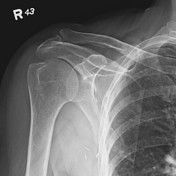

| Inferosuperior Axiolateral Shoulder | humerus is foreshortened - humeral head is distorted arm is not abducted 90 degrees from body |

| Grashey | Insufficient obliquity |

| Grashey | Excessive obliquity |

| Grashey | MCP is tilted posteriorly |

| Scapular Y-Lateral | ANATOMY: humeral head resting in the 'Y' of the acromion and coracoid process CRITERIA: vertebral border and lateral border of scapula are directly superimposed humeral head is aligned with body of scapula POSITIONING: pt's unaffected arm is abducted 90 degrees, pt in 45-60 degree anterior oblique CR perpendicular @ scapulohumeral joint (neer) CR angled 10-15 degrees caudal @ scapulohumeral joint |

| Inferosuperior Axial Shoulder | ANATOMY: lateral view of the proximal humerus in relation to the glenoid fossa CRITERIA: lesser tubercle in profile medially humeral head is in the center of VOI POSITIONING: affected arm abducted 90 degrees, hand rotated externally with hand supinated CR horizontal 25-30 degrees medial to the scapulohumeral joint |

| Posterior Oblique Grashey | ANATOMY: glenoid cavity in profile glenohumeral joint center of VOI CRITERIA: open glenoid cavity anterior/posterior rims of glenoid cavity are superimposed POSITIONING: pt in 35-40 degree posterior oblique CR perpendicular @ glenoid cavity |